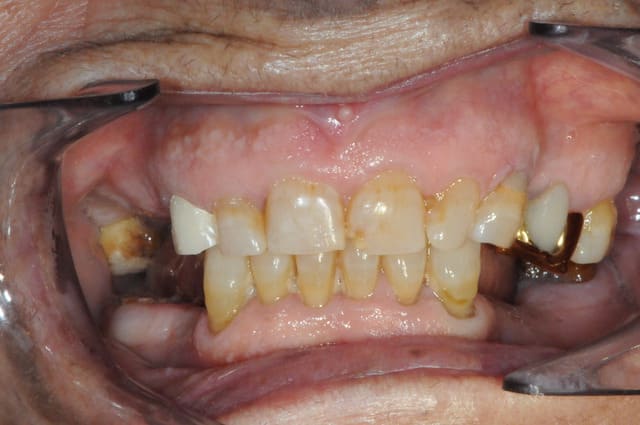

pour d57 je dirais bridge 13 14 15 16 meme si je ne suis pas sur (la couronne en or c'est sur qu'elle est naturelle)

si c'est ça c quand meme super bien fait

tu y es presque...

et aussi bridge en bas sur implant ? 45 47

en haut, céram sur 13 et bridge / implants et en bas,

effectivement bridge sur implant, mais à partir de 44.

la patiente de 87 ans était super pressée d'avoir au moins une partie de terminée.

les implants du coté gauches ont été posés en même temps qu'à droite.

il me faut encore extraire 37 et refaire le bridge 24-26 avant de finir le bridge sur implant en bas à gauche.